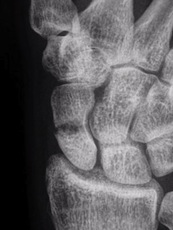

Die Diagnose eines Kahnbeinbruches ist schwierig und erfordert neben einer sorgfältigen klinischen Untersuchung u. U. mehrere Röntgenuntersuchungen. Wegen der gekippten Lage des Kahnbeins in der Handwurzel und seiner gekrümmten Form kommt das Kahnbein in den normalen Röntgenaufnahmen nur ungenügend zur Darstellung. Deshalb kann ein Kahnbeinbruch nicht immer durch Röntgen allein sicher festgestellt werden, v.a. wenn der Bruch unverschoben ist. Im Zweifelsfall kann die verletzte Hand nach 5-10 Tagen nochmals geröntgt werden. Oft lässt sich dann aufgrund der zwischenzeitlich eingetretenen Resorptionsvorgänge der Bruch erkennen.

Röntgenbilder in normaler Aufnahmetechnik

Spezielle Röntgenaufnahme zur besseren Darstellung des Kahnbeins

Die Diagnose wird anhand von Röntgenaufnahmen mit zusätzlichen Spezialaufnahmen des Kahnbeins gestellt. Eine Pseudarthrose ist deutlicher im Röntgenbild zu erkennen als ein frischer Bruch.

Normale Einstellung (links) und Spezialaufnahme (rechts)